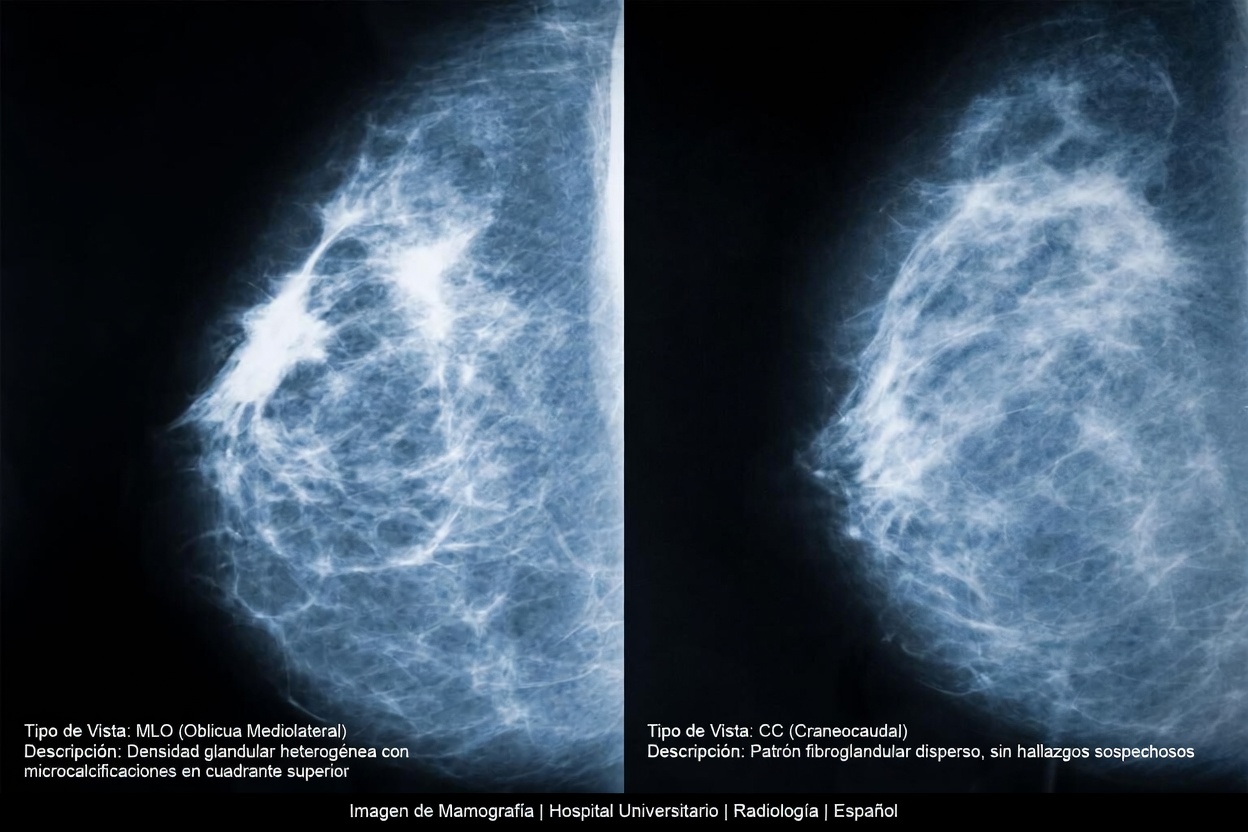

¿Por qué importa este dato? Porque en una mamografía, el tejido denso se ve de color blanco, y ciertas anomalías también pueden verse blancas. Eso puede dificultar la interpretación de las imágenes en algunos casos.

Heterogéneamente densa

- Puede ocultar algunos hallazgos

- Es común

Extremadamente densa

- Las imágenes pueden ser más complejas de interpretar

Por qué la densidad mamaria puede influir en el estudio

Hay algo que muchas mujeres nunca escuchan durante una revisión habitual: la mamografía tradicional funciona detectando contrastes entre los tejidos. El tejido graso suele verse más oscuro, mientras que el tejido denso aparece más claro.

Si una zona pequeña anormal también se muestra clara en la imagen, puede llegar a confundirse con el tejido denso que la rodea. Eso no significa que la mamografía no sirva. De hecho, sigue siendo una de las herramientas más importantes para la detección temprana del cáncer de mama.